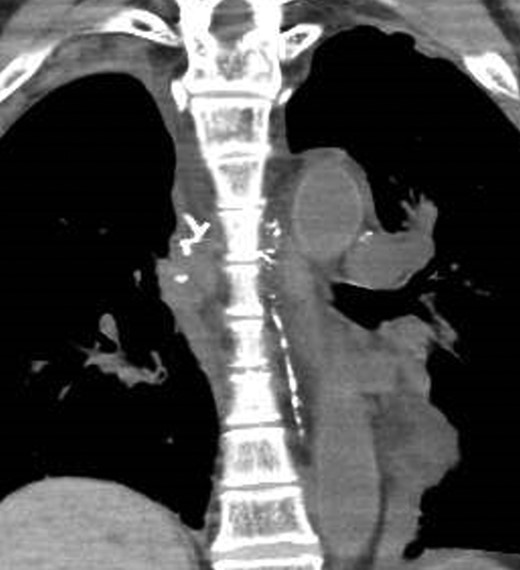

A 67-year-old man was referred to our hospital after transbronchial biopsy confirmed a diagnosis of non-small cell lung cancer. His physical examination findings and laboratory data were unremarkable. CT revealed a right upper lobe mass (diameter, 4.1 cm) in the apical portion; and thus, invasion of the right subclavian artery was suspected. On clinical staging, the tumor was T4N0M0, Stage IIIA. He underwent right upper lobectomy and mediastinal lymph node dissection via median sternotomy. Complete resection was achieved without concomitant resection of the right subclavian artery. The histological diagnosis was squamous cell carcinoma (pT3aN0M0, Stage IIB). Two drainage tubes were placed in the right thoracic cavity, and a total milky fluid volume of 2000 ml was drained on postoperative day (POD) 2. The volume of chylous drainage did not reduce with total parenteral nutrition. On POD 4, right-sided video-assisted thoracic surgery was performed 1 hour after intake of ice cream, to identify the site of chylous leakage. On intraoperative observation, multiple leakage sites were noted between the trachea and superior vena cava, and these sites were clipped and sealed with fibrin glue. However, the thoracic duct could not be identified in the right posterior mediastinum. After this surgical procedure, the volume of chylous drainage did not decrease. In addition, on POD 5 the patient complained of dyspnea. A chest X-ray revealed left pleural effusion, and a drainage tube was inserted into the left pleural cavity. LAG was performed to identify the leakage site, and the total amount of drained effusion from both sides was 3200 ml/day on POD 6 (2 days after the reoperation). The right inguinal lymph node was punctured with a 23-gauge needle under ultrasound guidance, and a total lipiodol volume of 7 ml was slowly injected under fluoroscopic guidance. CT after LAG revealed that the thoracic duct was located on the left side (Fig. 1). However, a day after LAG, the leakage site could not be clearly identified. Additionally, CT showed accumulation of lipiodol at the anterior mediastinum, which suggested the presence of chylous leakage from the thoracic duct tributaries in the anterior mediastinum (Fig. 2). Bilateral pleural effusion gradually decreased after LAG, and a low-fat diet was started on POD 20. The right and left chest drainage tubes were removed on POD 21 and POD 28, respectively. The patient was eventually discharged 30 days after the first surgery (23 days after LAG). CT performed 2 months after LAG revealed lipiodol retention in the thoracic duct and mediastinum. The patient remains asymptomatic without pleural effusion at 6 months after discharge.

A CT image 1 day after lymphangiography shows lipiodol accumulation in the anterior mediastinum and between the bilateral main bronchi and aorta.